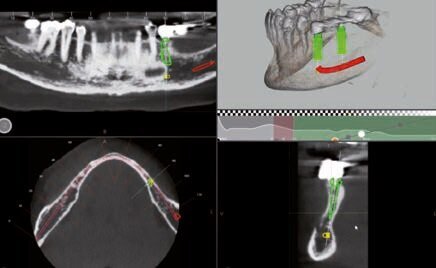

Fig. 4 - Progettazione impianto 35.

Fig. 5 - Progettazione impianto 37.

Dopo aver valutato con la paziente tutti i pro e i contro abbiamo deciso di prediligere la scelta dei REX PiezoImplant. È stata eseguita un’impronta digitale che è stata accoppiata tramite il software di progettazione all’esame radiografico tridimensionale. Sono stati scelti due impianti REX PiezoImplant 1,8 x 11. L’impronta digitale della situazione pre-intervento della paziente ci ha permesso di utilizzare quest’ultima (come ceratura diagnostica) per programmare il posizionamento implantare in modo protesicamente guidato. La pianificazione software della fase chirurgica e l’utilizzo di una guida per il corretto posizionamento dell’impianto “asse implanto- protesico”, ci hanno permesso non solo di ottenere il posizionamento implantare nel rispetto dello spessore osseo disponibile “asse anatomico” ma anche di ricercare la migliore soluzione protesica avvitata, “asse protesico”, per una sensibile riduzione del rischio di errore. È stata creata una dima chirurgica che ci ha permesso di riportare nel cavo orale la programmazione dell’inserimento implantare che avevamo pianificato virtualmente. La metodica Rex permette di utilizzare una slitta che prevede una chirurgia guidata con sistema Pilot utilizzando l’inserto W2. Sono state raccordate le due preparazioni e le abbiamo estese con l’inserto OT7S3 che ci ha permesso di ottenere una maggiore elasticità ossea.